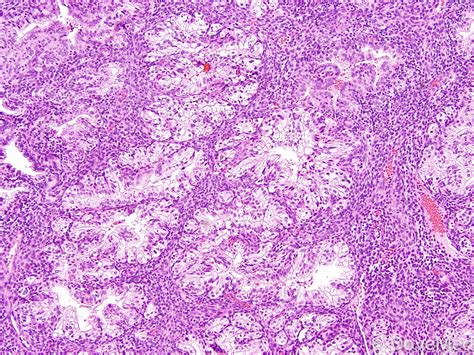

Spindle Cell Carcinoma is a rare histological subtype of squamous cell carcinoma (SCC). The term "spindle cell" refers to the morphological transformation of cancer cells that have lost their typical epithelial features and gained a mesenchymal (spindle-shaped) appearance. This process, often referred to as epithelial-mesenchymal transition (EMT), contributes to the tumor's aggressive biological behavior and its tendency for local invasion and rapid growth.

These tumors can arise in various anatomical locations, including the head and neck, the skin, the esophagus, and the respiratory tract. Because the cells appear non-epithelial under a microscope, pathologists often rely on specialized immunohistochemistry stains to confirm the diagnosis and distinguish it from other conditions like sarcomas or melanomas.

Accurate diagnosis is the cornerstone of effective management. Because Spindle Cell Carcinoma can be easily misidentified, the diagnostic process usually involves a multi-step approach.